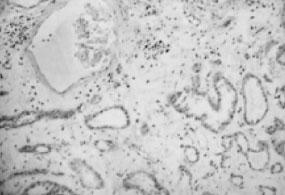

2.光镜检查 肾间质高度水肿,偶可见到肾静脉分支中有血栓形成,肾小球毛细血管扩张淤血,并可见节段性粒细胞浸润和微血栓形成。肾小管上皮细胞空泡变性,刷状缘脱落,而小动脉无明显病变(图5—7,图5—8)。慢性期,肾间质纤维化,肾小管萎缩,肾小球缺血。

图5—8 肾静脉血栓,肾间质水肿